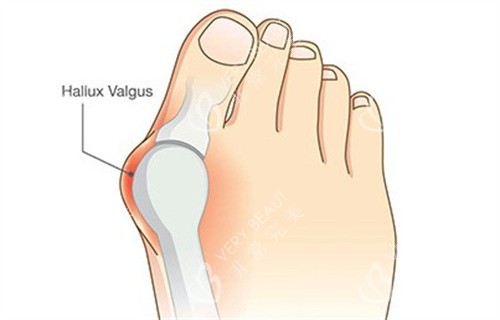

在追求美丽与健康的道路上,大脚骨问题成为了许多人的困扰。它不仅影响足部美观,还可能引发疼痛与功能障碍。北京广济医院凭借其在大脚骨治疗领域的卓然表现,成为了众多患者的信赖之选。下面,让我们深入了解一下这家医院。

医院引进了海内外可靠的医疗设备和技术,如智能 3D 检测系统、HD - 超小创口拇外翻矫正术等。智能 3D 检测系统能够对拇外翻足进行多方面评估、科学分类、分型,为制定个性化治疗方案提供有力支持。而 HD - 超小创口拇外翻矫正术具有毫米微切口、无需缝合、不留疤痕、不影响生活、随治随走、无需住院等优势,大大提高了手术的精细度,缩短了手术时间和改善周期。

医院重视患者的个体差异,针对不同病情和体质的患者,制定个性化的治疗方案。对于轻度外翻患者,可能建议采用支具调整结合改善训练;而中重度患者则需通过手术矫正骨骼和软组织平衡。这种个性化的治疗方案满足了患者的需求,确保了手术结果的满意度和自然度。